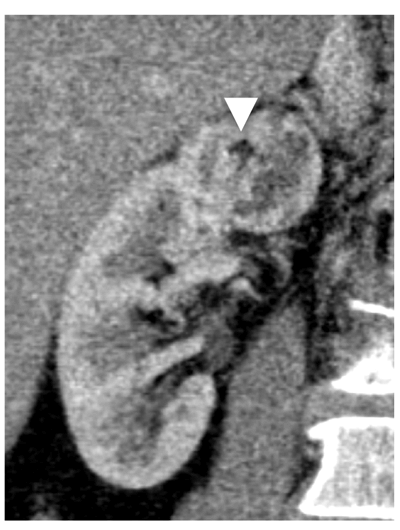

Hyperdense cysts contain colloid or haemorrhagic material and therefore appear ‘bright’ on pre-contrast imaging, with attenuation values characteristically >70HU. Hyperdense cysts should typically measure <3cm in diameter, appearing homogenous, round and thin-walled, with enhancement gradients <10HU (Figure 8) [13].

Figure 8: Hyperdense cyst. Attenuation value 75HU on unenhanced CT (left).

No significant contrast enhancement on nephrographic phase, 80 HU (right).